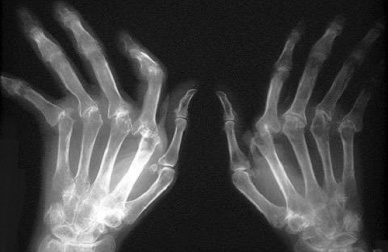

As áreas mais afetadas pela artrite reumatoide são os pulsos, os cotovelos, os ombros, os dedos das mãos e dos pés, os quadris, os tornozelos e os joelhos.

Além disso, podem aparecer também nódulos reumatoides, nódulos na pele (especialmente no dorso das mãos e dos pés) ou no interior do corpo. A inflamação dá lugar à deformação das articulações quando a doença está em um estado avançado.